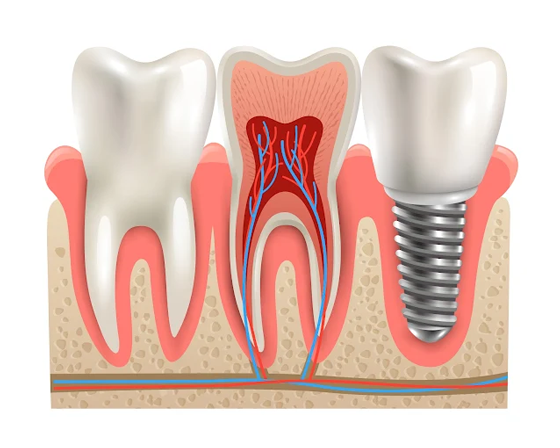

Dental Implants in Fulwood and Preston Lancashire

Missing teeth can impact confidence and daily life. Lifestyle Dental specializes in dental implants in Fulwood, dental implants Preston Lancashire, full smile restoration, and long-lasting solutions for missing teeth.